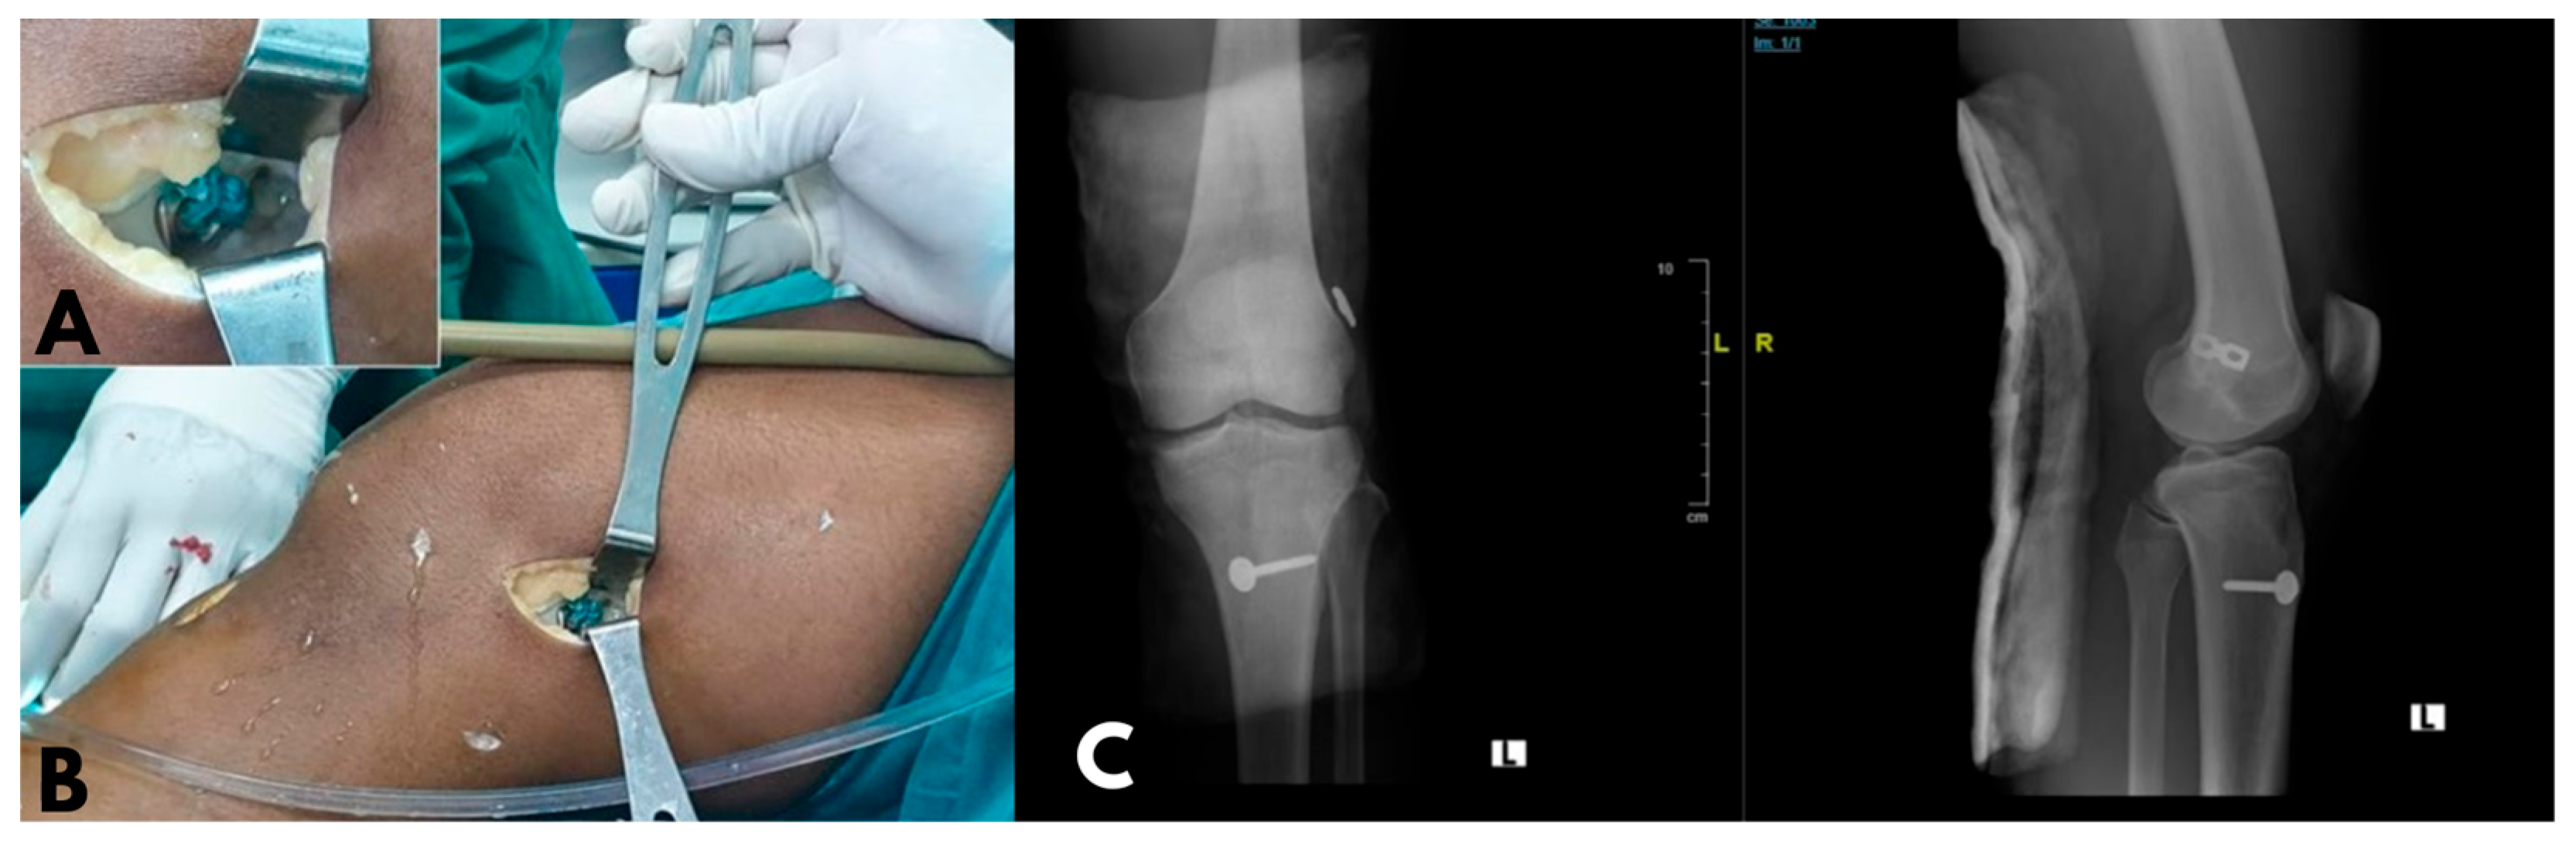

2.5. Operative Technique